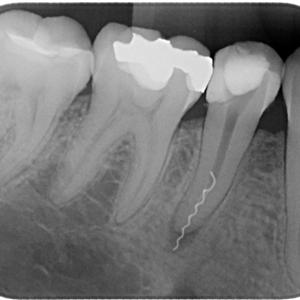

I O P A = Intra oral peri-apical view (Small x.ray of 3 to 4 diseased teeth)

l Any kind of Dental and Gum Problems like Carries, Peri-apical Infections, Cysts Etc can be detected clearly and more confidentaly through direct Digital I O P A X.Rays.

l Palatal diseases, abscesses, salivary duct stones, dental / palatal cysts, infection / Carries of teeth, fracture of teeth / jaw, cancer of mouth / mandible etc can be diagnosed more confidently and accurately with this technology.